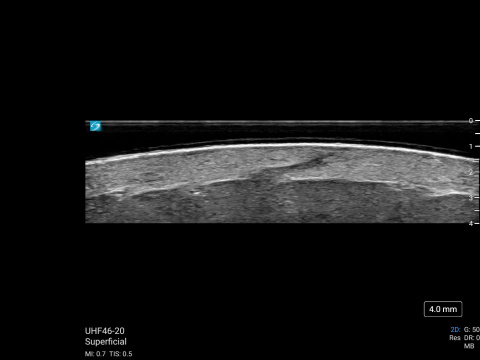

MSK Market Development Director, Daniel Shelton, shows off the capability of Sonosite UHF 46-20 with scans of a hair follicle and a vein. The scans were then illustrated to reveal details less obvious to the non-clinical eye.

Vein (small superficial branch), the cephalic on the distal 1/3 forearm